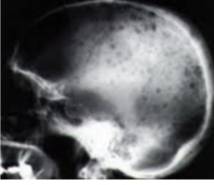

안타깝게도 다발골수종의 정확한 발병 원인이 알려지지 않아, 예방법은 없다. 다만, 무증상 단계에서 건강검진 시 M단백이 발견되는 경우가 있는데, 일찍만 발견하면 치료 예후가 훨씬 좋은 만큼 정기적인 건강검진이 악화를 막는 최선의 예방책이 될 수 있다. 혈액·소변 검사에서 M단백이 발견되면 골수검사 등 추가 검사들을 통해 다발골수종으로 확진하고, 전신 CT(컴퓨터단층촬영)나 MRI(자기공명영상) 등 검사로 골 침범 병변이 있는지 등을 확인하게 된다.